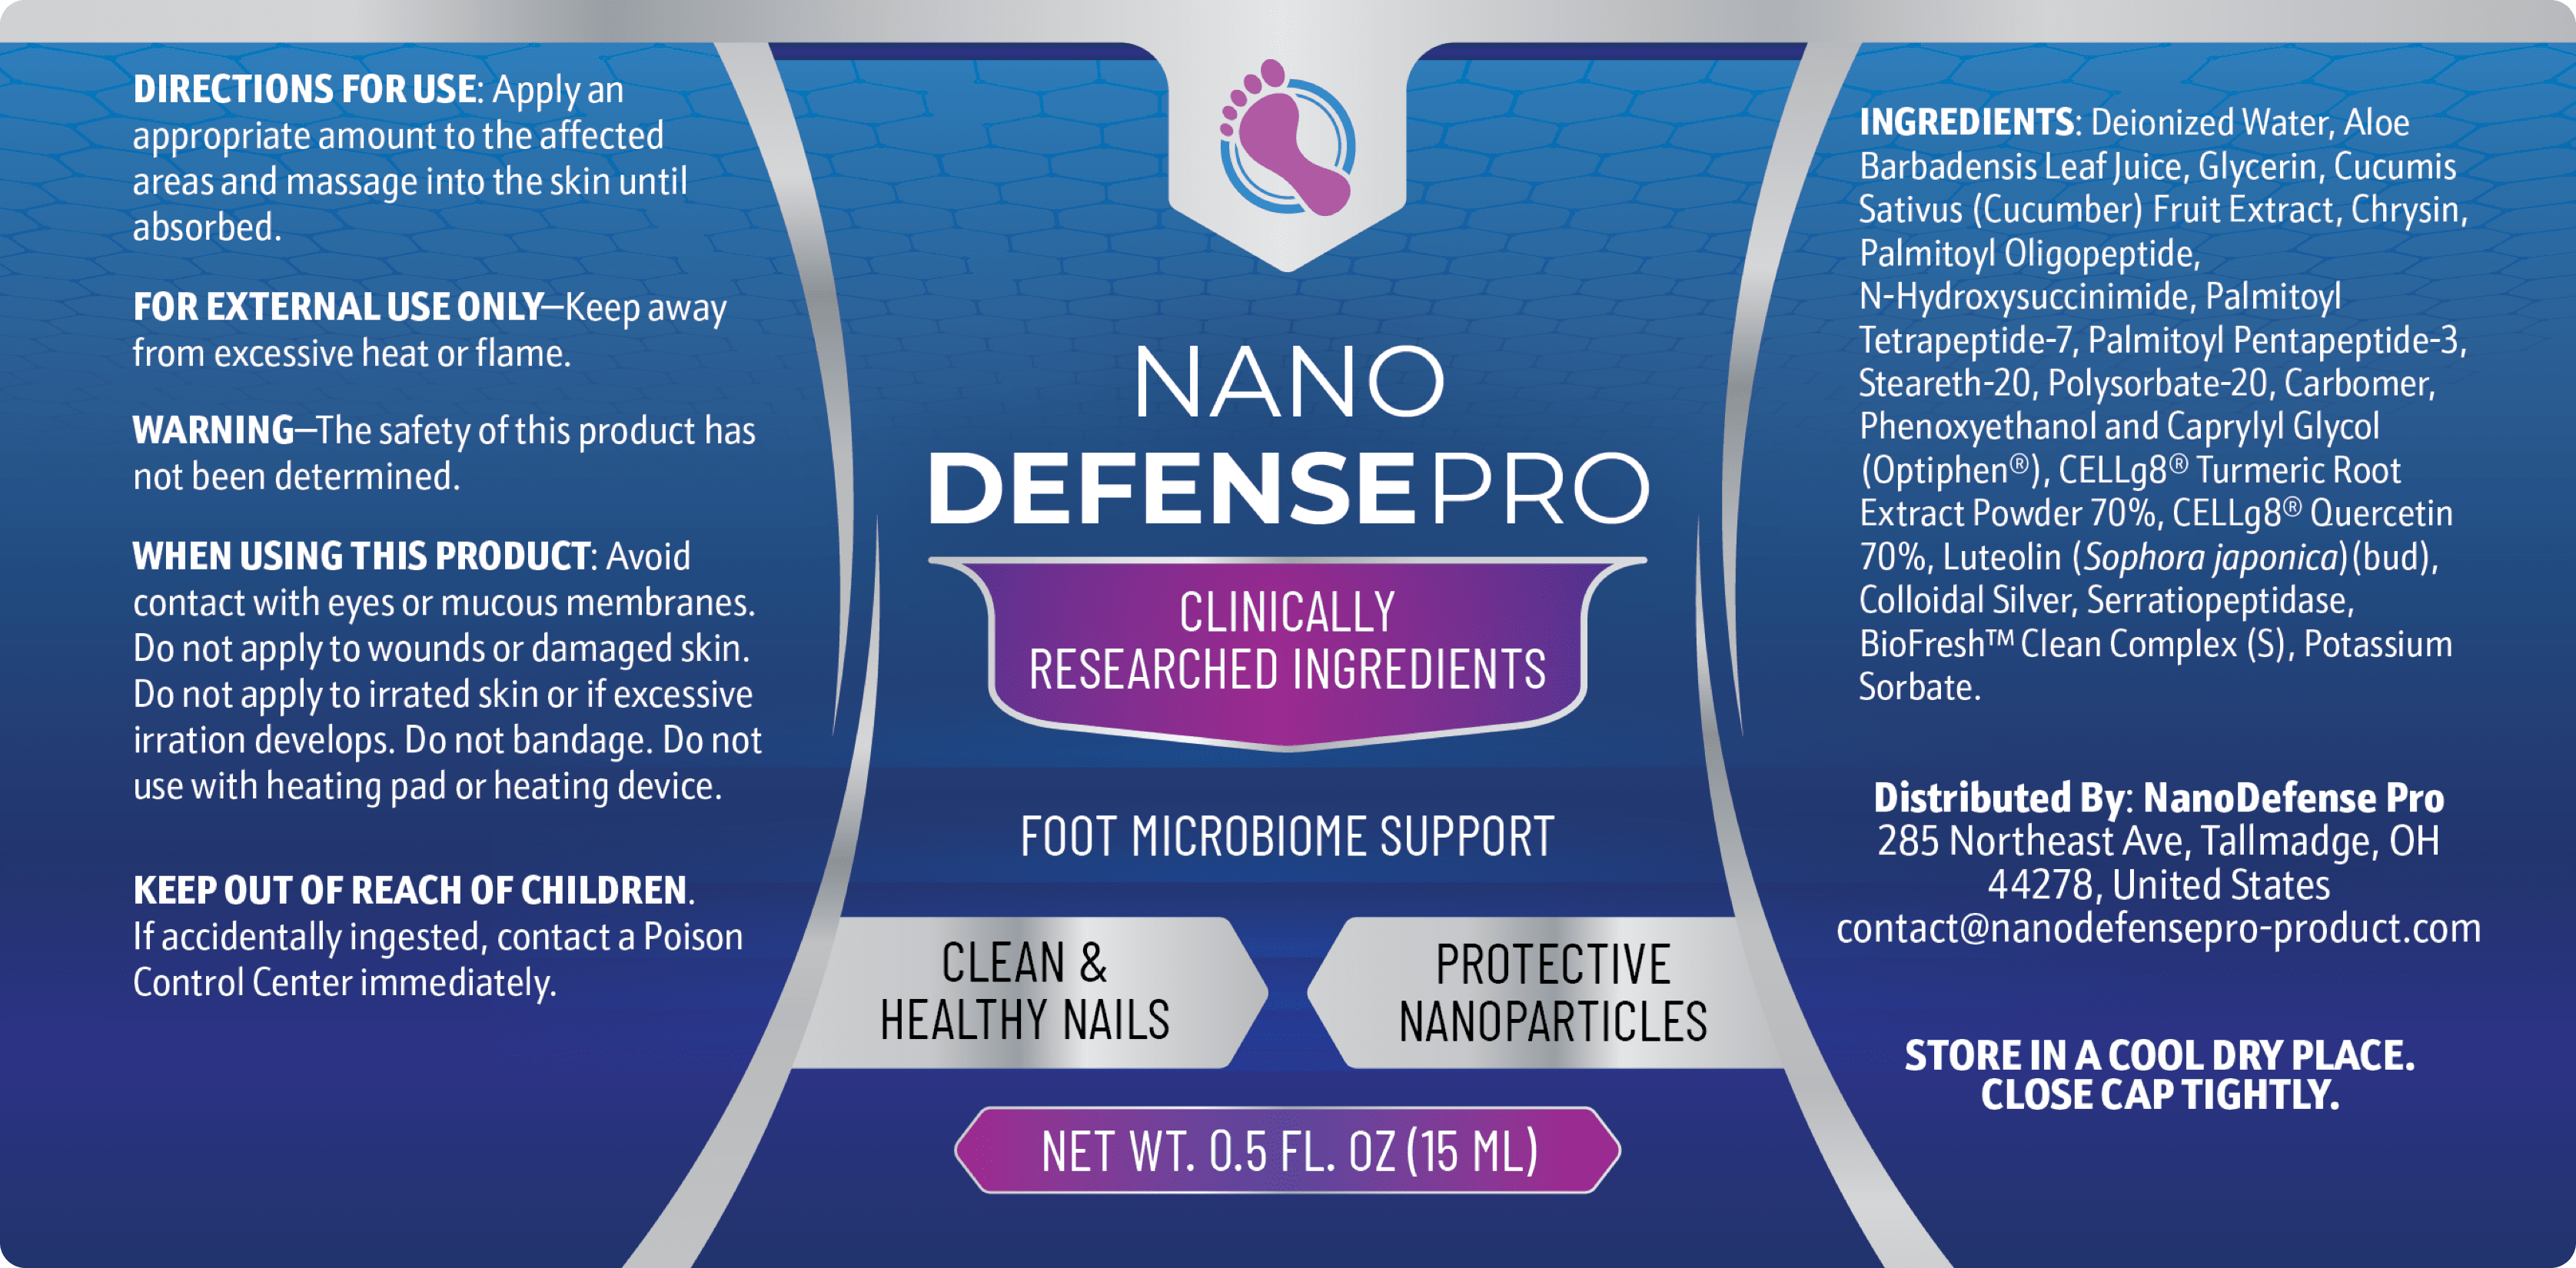

A perfectly dosed proprietary blend of selected nano-

ingredients, carefully

mixed to complement one another into a powerful formula and contribute to

the health of your nails and skin.

Nano-Silver

Nano-Curcumin

Nano-Quercetin

Luteolin

Deoxyribonuclease

Cape Aloe

NanoDefense Pro is a special formula made of nano-ingredients, which are 1000x smaller than a regular molecule. Thanks to this, these extremely small particles are capable of delving deep, nurturing our skin and nails at their very core.

NanoDefense Pro has been designed for all ages and medical conditions. All of the ingredients have been proven to be safe in clinical trials and are constantly tested for purity and to ensure against toxins and contaminants.

As always, if you currently have a medical condition or you’re taking other prescription medication, we advise you to show a bottle of NanoDefense Pro to your doctor before you use it, just to put your mind at ease.

Simply apply NanoDefense Pro to the problem area for 60 seconds a day.

Inside every single drop of NanoDefense Pro is a proprietary formula of strong nano-ingredients, custom-made to nourish your skin and nails deeply.